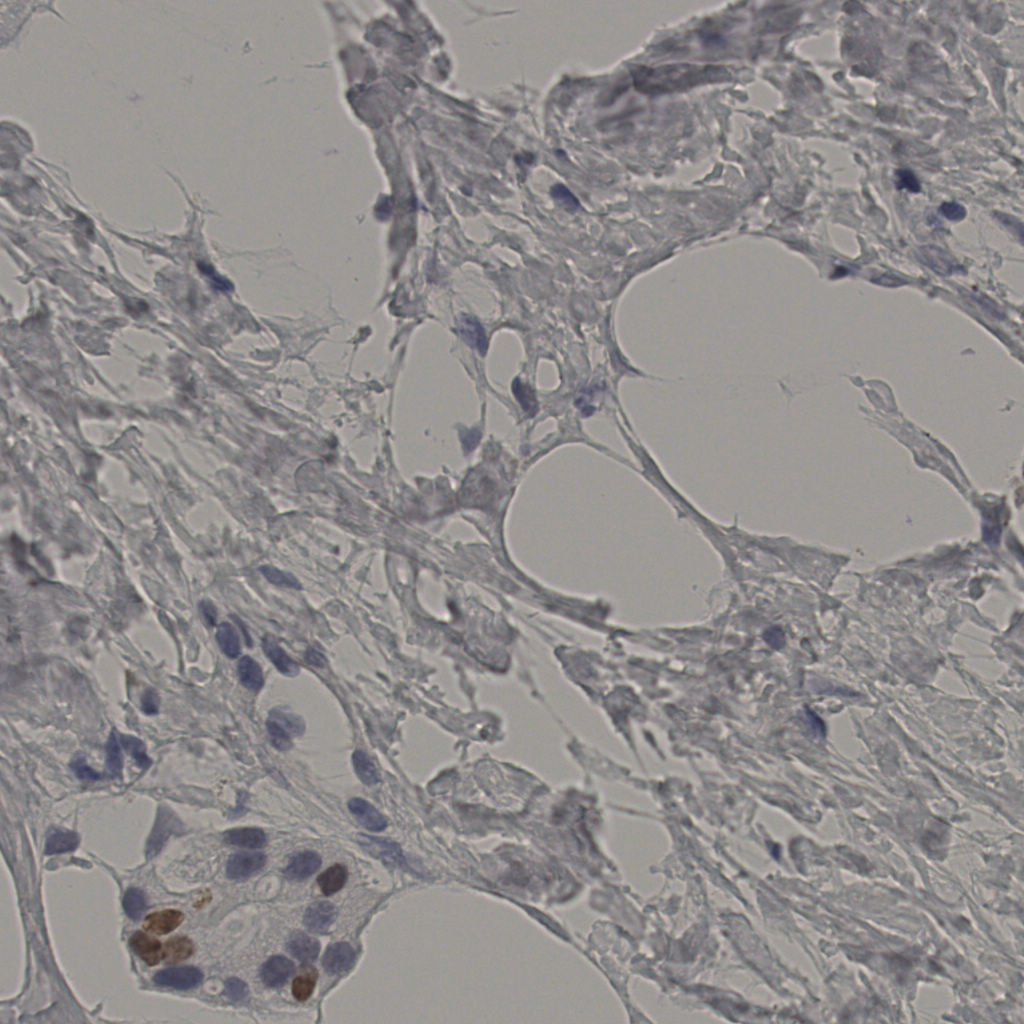

Ki67 指数

阴 19502 阳 1093

20240398Ki-67.ndpi

slice_20_46_x17920_y41216.png